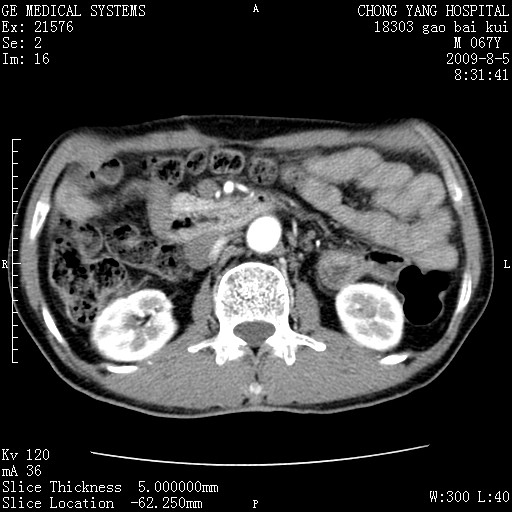

这个也过了,考虑胰腺钩突癌或壶腹癌,不除外胰管粘液乳头瘤伴胰管扩张,肝内胆管积气.

1)考虑胰头癌或壶腹癌并胰管扩张。2)肝外胆管扩张、积气,胆囊影未见;考虑术后改变。3)胃壁增厚?建议必要时行胃镜检查。

虑胰腺钩突癌或壶腹癌,不除外胰管粘液乳头瘤伴胰管扩张,肝内胆管积气.

考虑胰头癌并十二指肠受侵。